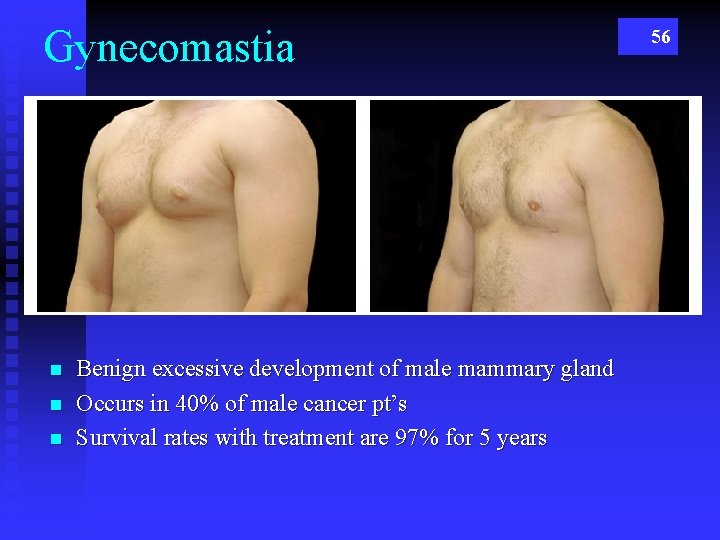

Gynecomastia n n n Benign excessive development of male mammary gland Occurs in 40% of male cancer pt’s Survival rates with treatment are 97% for 5 years 56